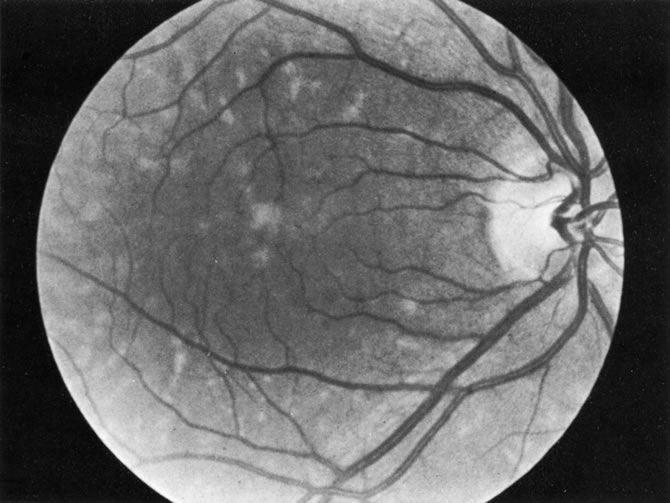

Some retinal dystrophies and degenerative processes can simulate a retinochoroiditis. Vitreous cells may occur in cases of retinitis pigmentosa. Pigmented paravenous retinochoroidal atrophy has a distinctive pattern of pigmentary deposits surrounding retinal veins; it may occur as an idiopathic degenerative disorder or sometimes as a sequela of ocular sarcoid. Fundus flavimaculatus is a rare autosomal recessive dystrophy that is usually detected in the third decade of life. It produces typical comma-shaped, yellowish retinal pigment epithelial opacities in the posterior pole, but it does not involve the macula. It can simulate a diffuse choroiditis (Fig. 24). Myopic degeneration can produce small, white, posterior pole spots that can simulate a posterior choroiditis. Peripheral fundus “paving stone” degeneration is rarely confused with an inflammatory process. These lesions show no evidence of retinal or vitreal inflammation and are quite common.54

Fig. 24. Fundus flavimaculatus. Note comma- or fish-shaped yellowish Figures at the level of pigment epithelium.